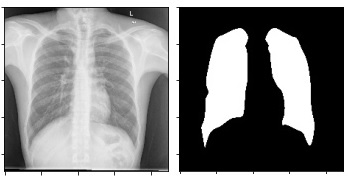

lung-segmentation